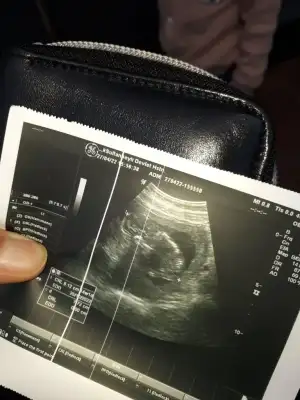

Bende kız hissediyom renkli ultrasonda baya kıza benziyodu ama doktor daha bişey demediiyice gizlemişbence Prenses canım sen ne hissediyorsun

maşallah, sanki erkek gibi ama çok anlaşılmıyor ileriki hafta görüntülerini de at canımBana da bakar mısın canım 7 haftalık burda karından![]()

PrensesBu da arkadaşımın buna da bakabilir misiniz karından 6 haftalıkmış bu Eki Görüntüle 3059022